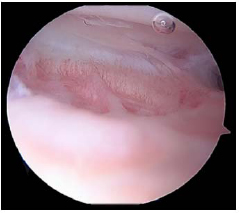

All the patients were placed in the supine position on an operating table. A tourniquet was applied to the thigh with the knee in the maximum possible flexion position to minimize capture of the quadriceps femoris muscle. The procedure was performed using the three-portal technique with two standard anterolateral and anteromedial portals in addition to the accessory superolateral portal [8, 9]. Tissue adhesions were identified (Fig. 1) and debrided using a radiofrequency device (Arthrocare, Arthrocare Sports Medicine, USA) (Fig. 2). Subsequently, gentle manipulation was performed by applying slight pressure on the tibial tubercle to avoid fractures or disruption of the extensor mechanism. After the operation, continuous passive motion was immediately initiated.